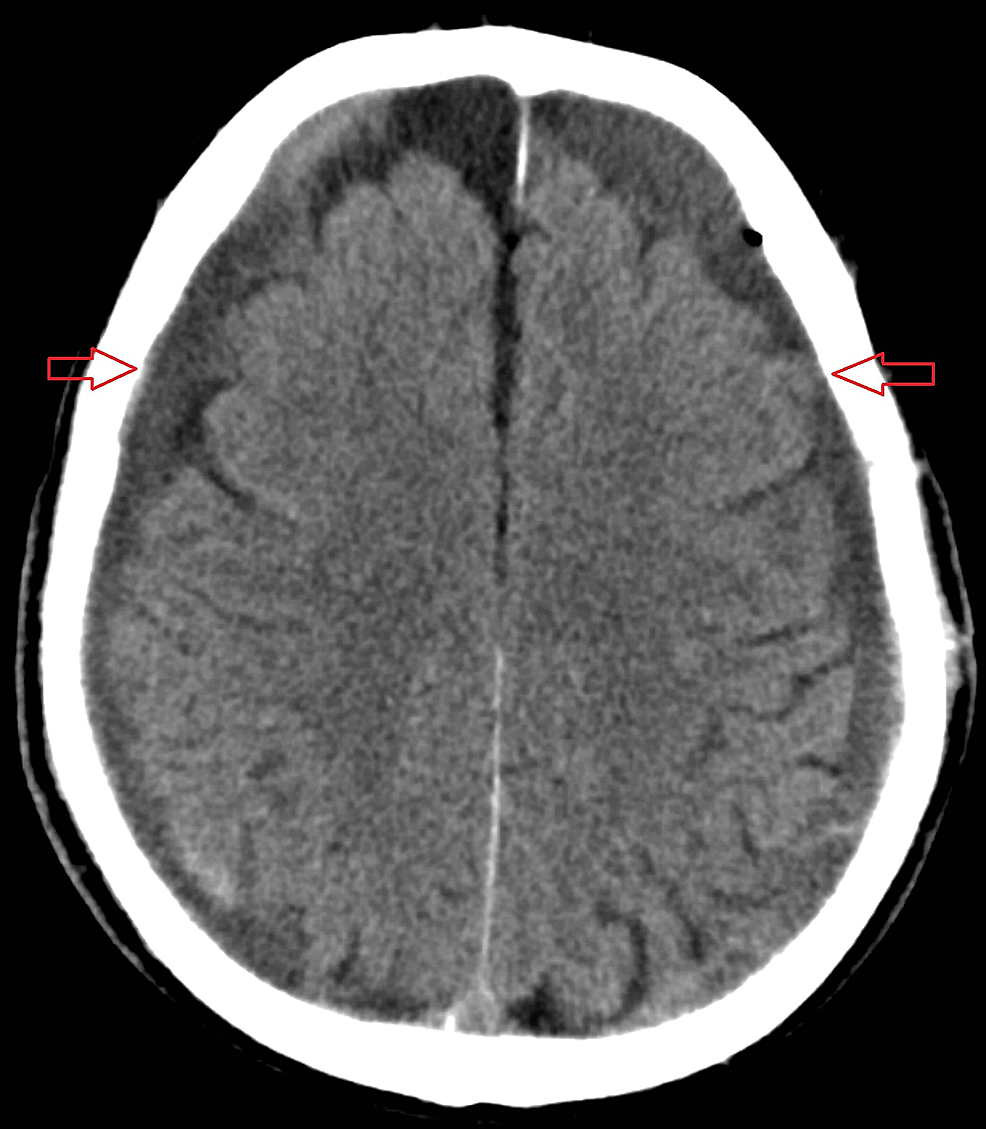

A 70-year-old male initially presented to the local hospital following an alleged assault in which he sustained a minor head injury. The Glasgow coma score (GCS) on presentation was 15. Initial computed tomography (CT) scan of his brain was unremarkable. He was discharged but developed worsening headache and left-sided weakness one month later. He represented to the hospital and a repeat CT showed bilateral acute on chronic subdural haemorrhages (Figure 1).

The patient was taken to the theatre for bilateral craniotomies and evacuation. The dura was closed in a non-watertight fashion. Post-operatively he failed to recover. The GCS was three and his pupils were non-reactive to light. He was taken for an emergency CT brain scan which showed tension pneumocephalus with the presence of the Mount Fuji sign (Figure 2). He was immediately taken back to the theatre for a re-exploration of his left-sided craniotomy. The left wound was re-opened and the frontal lobe was noted to be under pressure and was decompressed. Warm saline was used to fill the cavity and the dura was closed to give a water-tight seal. A drain was placed and the craniotomy wound was closed.